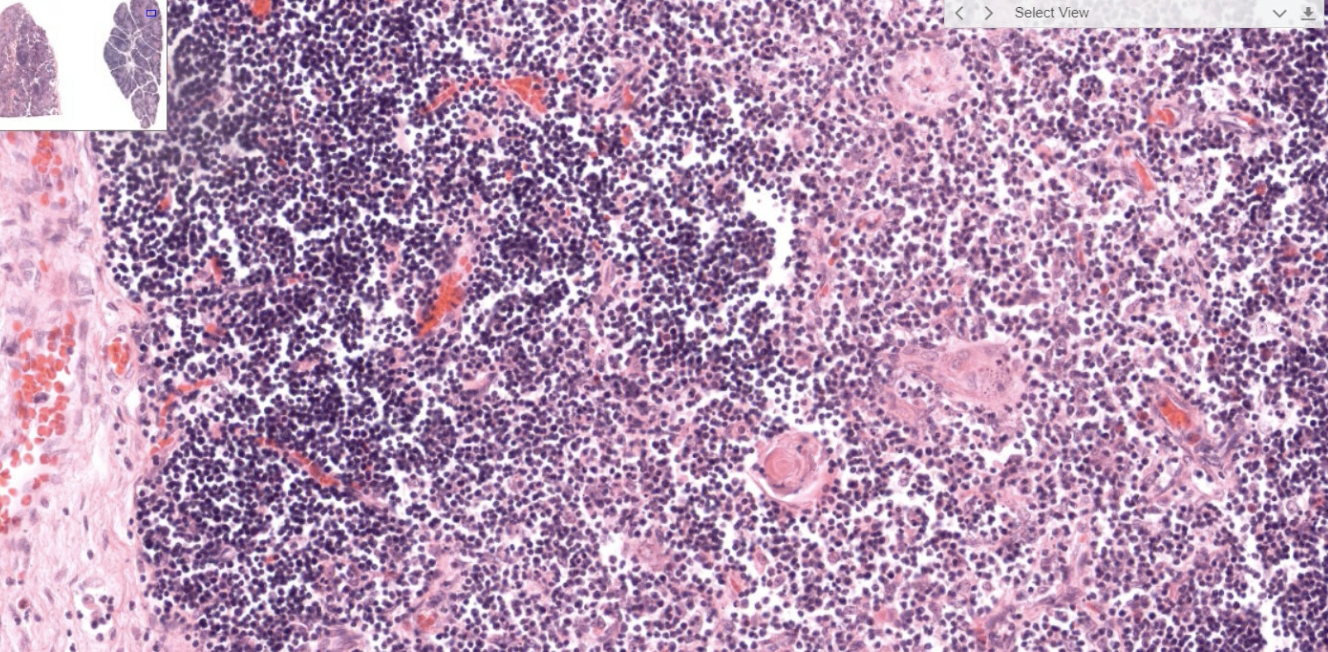

- Capsule

- Afferent → Subscapular sinus → Trabecular sinuses → Medullary sinuses → Efferent

血管,淋巴細胞鑽出到germinal center 活化

Warning

In all lymphoid organ except the thymus

形成抗體

GC: Germinal center (產生抗體, B cell)

MnZ: Mantle zone(T cell)

粉紅色: Reticular cell